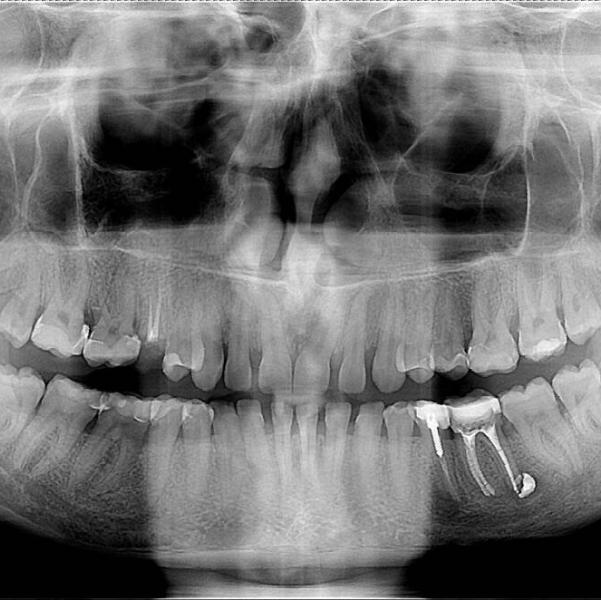

девочки стоматологи. помогите пожалуйста. интересует левая часть снимка, левая 6капод временой пломбой уже 3 месяца. уже как две недели есть чувство онемения слева на челюсти и жжения. нет ли там какого нибудь воспаления. спасибо Вам!

Вероятнее всего к хирургу вам(пломбировочный материал вывели за верхушку корня.где лечили?

Это вам так канал пломбировали? У меня несколько лет назад перепломбировка разъела челюсть (не знаю как по научному, но выглядело на снимке также). Прикусывать было больно и онемевшая челюсть была. Делали несколько уколов в десну, чтобы облегчить. Онемение больше года проходило, а болеть при прикусывании перестало где-то через месяц. Это косяк стоматолога

@rusro ну это я в курсе. как мне врач сказал это с целью лечения, лечим периодонтит